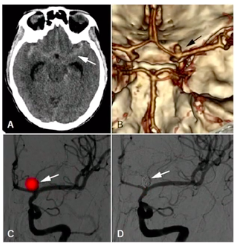

Exame de escolha na emergência na HSA e sensibilidade

A

• TC de crânio

• Sensibilidade próxima a 100% nas primeiras 6h e < 60% após 5 dias

• Angiotomo/angiorressonância é importante para localizar aneurisma

12

Q

Padrão ouro diagnóstico e terapêutico da HSA

Angiografia distal